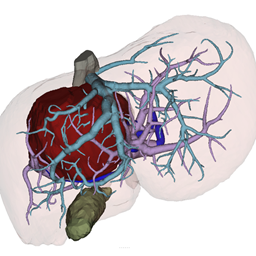

Master Thesis – Geometric Deep Learning for Liver Resection

This project focuses on pre-operative liver resection risk analysis using geometric data (meshes, point clouds). Such representations support advanced AR/VR tools and provide a realistic, intuitive understanding of surgical resection planning.

(Manual) Vessel Segmentation

We are looking for a student assistant („Hiwi„) for carrying out vessel segmentation in tomographic image data. After the segmentation, a transformation into 3D surface models should be carried out, including postprocessing of the surface meshes.

Vessel Tree Analysis

We want to develop an automatical vessel tree analysis tool for medical vascular structures. This is important for tumor surgery planning (which vessel should be spared? which vessel is at risk by the tumor location? …) but also for stroke analysis (which vessel supporting the brain might be hampered?).